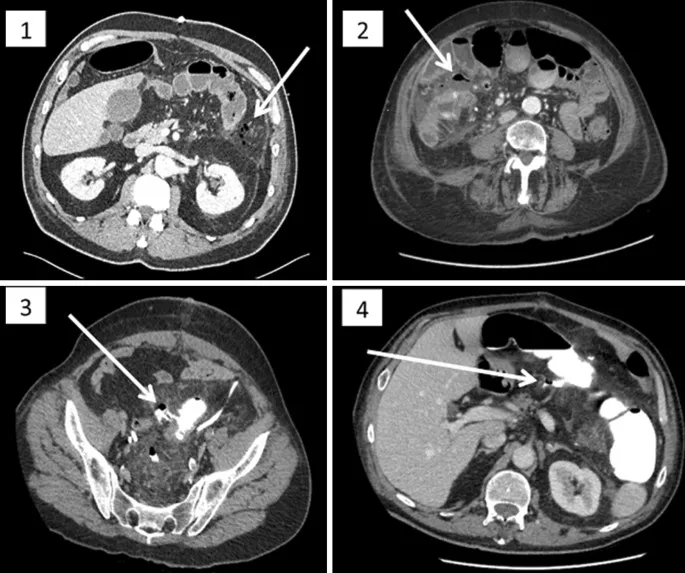

- CT A/P with IV/PO contrast is the gold standard.

- Identifies transition point, etiology, and complications (e.g., ischemia, perforation).

- Diagnosis: Abdominal CT with oral/IV contrast is the gold standard. Look for extraluminal air or contrast extravasation.